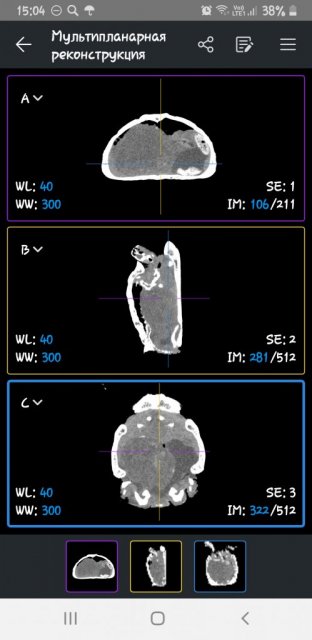

Александр Вдовин Ваше имя: Александр Локация: РФ, Самара Опубликовано: 26 августа 2024 Автор Опубликовано: 26 августа 2024 К сожалению, никто не может поставить четкий диагноз моей черепахе( Спасибо Бохиной Оксане Дмитриевне из Саратова: она откликнулась онлайн быстрее всех Спасибо Наталье Юрьевне из Самарской клиники "Симсон" за то, что она первая из ветеринаров обратила внимание на тяжелое дыхание черепахи и сделала рентген в 3 проекциях. К тому же согласилась делать процедуры по назначению легендарного орнитолога Васильева.К сожалению, не могу на него выйти Спасибо Стребковой Валерии Николаевне за информацию о содержании и попытки помочь, но я боюсь мучить питомца процедурами, которые не умею делать, тем более без четкого диагноза. Возьмется ли другой ветеринар в Самаре делать эти процедуры по назначению Валерии Николаевны я не знаю и будет ли от них толк. Черепаха же не закричит и не заплачет, когда ей больно( Черепаха моя пока греется под лампой. А я ожидаю звонка из Самарской клиники, которая после моих слезных просьб согласилась сделать КТ, но без описания. Записали меня пока на четверг на 13.00. Обещали позвонить, если освободится окошко раньше. Клиника, слава Богу, недалеко от моего дома. В случае звонка я туда быстро подскочу. Постараюсь никуда не отлучаться Валерия Николаевна сказала, что каловые массы на рентгене дожны быть видны, но их нет

Александр Вдовин Ваше имя: Александр Локация: РФ, Самара Опубликовано: 29 августа 2024 Автор Опубликовано: 29 августа 2024 Каловые массы даже очень большой плотности и большИх размеров на рентгеновском снимке могут быть абсолютно не видны. Узнал я об этом на днях благодаря небезразразличной участнице форума Дарье, поделившейся со мной снимками рентгена(не показал ничего, кроме газов в желудке), КТ(показала наличие в кишечнике комка с денсивностью в центре, как у костной ткани) и постоперационными разъяснениями врача(сказал, что это были очень плотные каловые массы), несмотря на боль об утрате питомца Сегодня у нас КТ. Я всё же ещё надеюсь, что у нас проблема не в кшечнике,т.к. газов в ЖКТ у нас на рентгене не видно. Также надеюсь на помощь с постановкой диагноза моей черепачке после КТ. Описания КТ нам не обещали, а обещали лишь диск

Александр Вдовин Ваше имя: Александр Локация: РФ, Самара Опубликовано: 30 августа 2024 Автор Опубликовано: 30 августа 2024 Сжатая ZIP-папка с КТ весит 118мб Сюда можно 5мб К сожалению, не могу скинуть сюда результат К Наталье Юрьевне в "Симсон" попаду только 1.09.2024 в 14.00 Черепаху не кормлю, купаю. Пьет мало. В туалет так и не ходит. Задние лапы не использует

Александр Вдовин Ваше имя: Александр Локация: РФ, Самара Опубликовано: 30 августа 2024 Автор Опубликовано: 30 августа 2024 Очень опасно сливать мочу, если она с солями? Я смотрел КТ. Там как-будто кишечник пережат мочевым пузырем, на дне которого много солей. Отправил видео в ТГ Наталье Юрьевне. Пока она ничего не ответила Подскажите может ли мочевой пузурь среднеазиатской черепахи раз дуться до таких размеров, что начинаться ближе к передней части черепахи?

Александр Вдовин Ваше имя: Александр Локация: РФ, Самара Опубликовано: 30 августа 2024 Автор Опубликовано: 30 августа 2024 (изменено) Купаю. Сегодня во время купания не давал ему пить. Не знаю правильно ли это. Также делал гимнастику задних лапок. Тоже не знаю эффективно ли это и не противопоказано ли. На последнем снимке(выше) видно как-будто камушек застрял в мочеиспускательном канале и рядом с резко белым фоном резко черный, будто воздух в расширенном из-за камушка мочеиспускательном канале.На фото видно плохо, но в программе на компьютере это очень заметно На фото видно где крестик. Может ли мочеиспускательный канал располагаться так далеко от хвоста? К сожалению в открытых источниках мало информации об этом Какое успокоительное средство(сильнодействующее) ему можно вколоть, и, главное, за какое время до процедуры, если ветеринар, или даже орнитолог, попробуют слить мочу с помощью катетера? Читал статью о премедикации рептилий, но именно о сухопутной черепахе(с её медленным метаболизмом) там ни слова Изменено 30 августа 2024 пользователем Александр Вдовин Дополнение